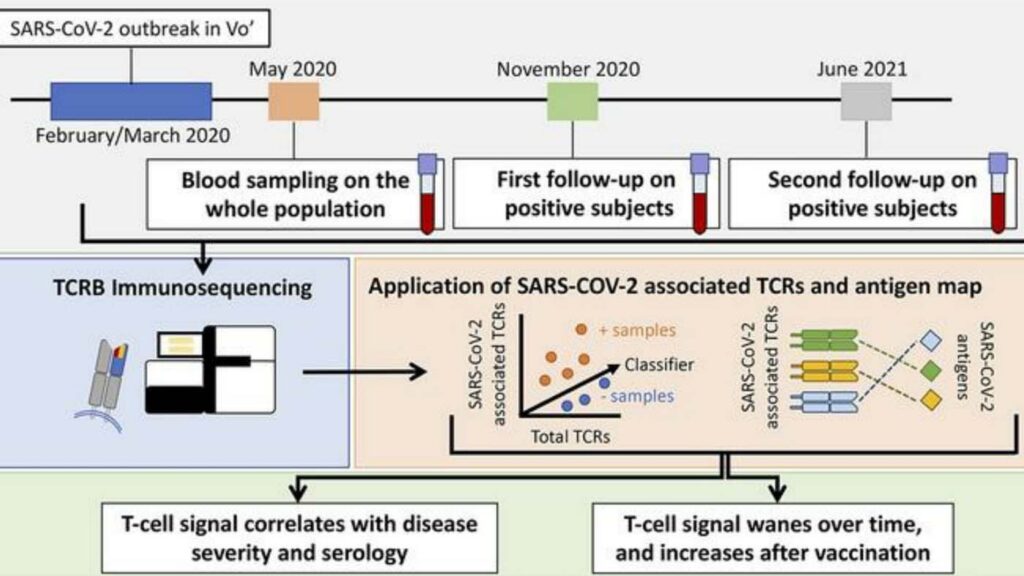

Longitudinal analysis of T cell receptor (TCR) repertoires reveals shared patterns of antigen-specific response to SARS-CoV-2 infection

T cells play a prominent role in the immune response to viral diseases, but their role in subsequent immunity to SARS-CoV-2 infection remains poorly understood. This research studied the assortments (repertoires) of TCRs in an Italian population following a SARS-CoV-2 outbreak. An individual’s TCR repertoire changes as immunity is developed following exposure. Samples taken at 2, 9 and 15 months found elevated levels of TCRs associated with SARS-CoV-2, demonstrating the T cells’ central role in mounting a persistent immune defense against SARS-CoV-2.